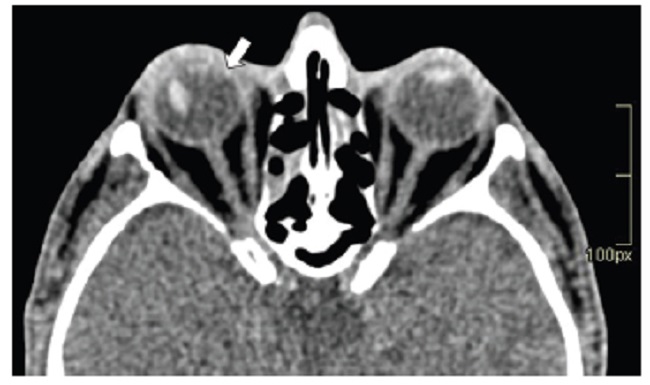

Las calcificaciones oculares y el material médico se pueden confundir con cuerpos extraños u otras lesiones orbitarias1. Las localizaciones típicas de las calcificaciones permiten diferenciarlas de cuerpos extraños hiperdensos. Las más frecuentes son las calcificaciones trocleares, las placas esclerales, las drusas del nervio óptico y la ptisis bulbi. Las primeras tienen localización superomedial dentro de la órbita (Fig. 13), en la tróclea del músculo oblicuo superior, aunque se pueden observar en todas las edades, hay mayor prevalencia de calcificaciones trocleares en pacientes con enfermedades autoinmunes y niveles elevados de fosfatasas alcalinas. Las placas esclerales se localizan en los sitios de inserción de los músculos rectos medial y lateral (Fig. 14) y son más comunes en los pacientes ancianos. Las calcificaciones que ocurren cerca del disco óptico se conocen como drusas del nervio óptico (Fig. 15), las cuales se asocian a degeneración macular y pueden ser causa de pseudopapiledema benigno. La ptisis bulbi es una atrofia y calcificación del globo ocular como secuela de enfermedades infecciosas, inflamatorias o traumáticas previas (Fig. 16) (1,11. Los imitadores de lesiones abiertas del globo ocular incluyen las deformidades como coloboma, estafiloma y el globo ocular elongado por glaucoma o miopía (Fig. 17). Las masas orbitarias y los hematomas también pueden alterar el contorno del globo ocular y asociarse a calcificaciones o relacionarse con desprendimiento de retina (Fig. 18) (1,6,8,11.

Los cambios postratamiento y los dispositivos orbitarios también pueden malinterpretarse como patologías traumáticas. Dentro de estos cambios se incluyen la faquectomía con reemplazo del cristalino, las hebillas esclerales (Figs. 19 y 20), las inyecciones intraoculares de aceite de silicona, la retinopexia neumática y las prótesis de globo ocular1,6,11. Para diferenciar la silicona intraocular de hemorragia se ha propuesto la medición de las UH, siendo la atenuación > 100 UH sugerente de silicona y < 90 UH de sangre11 (Fig. 20).